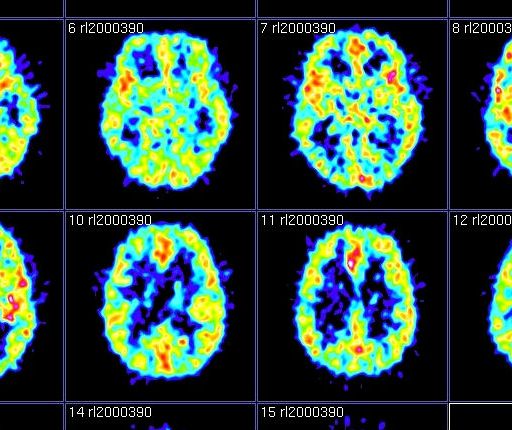

Animal studies allow neuroscientists to study the brain at the level of individual neurons, unlike human brain-imaging studies.